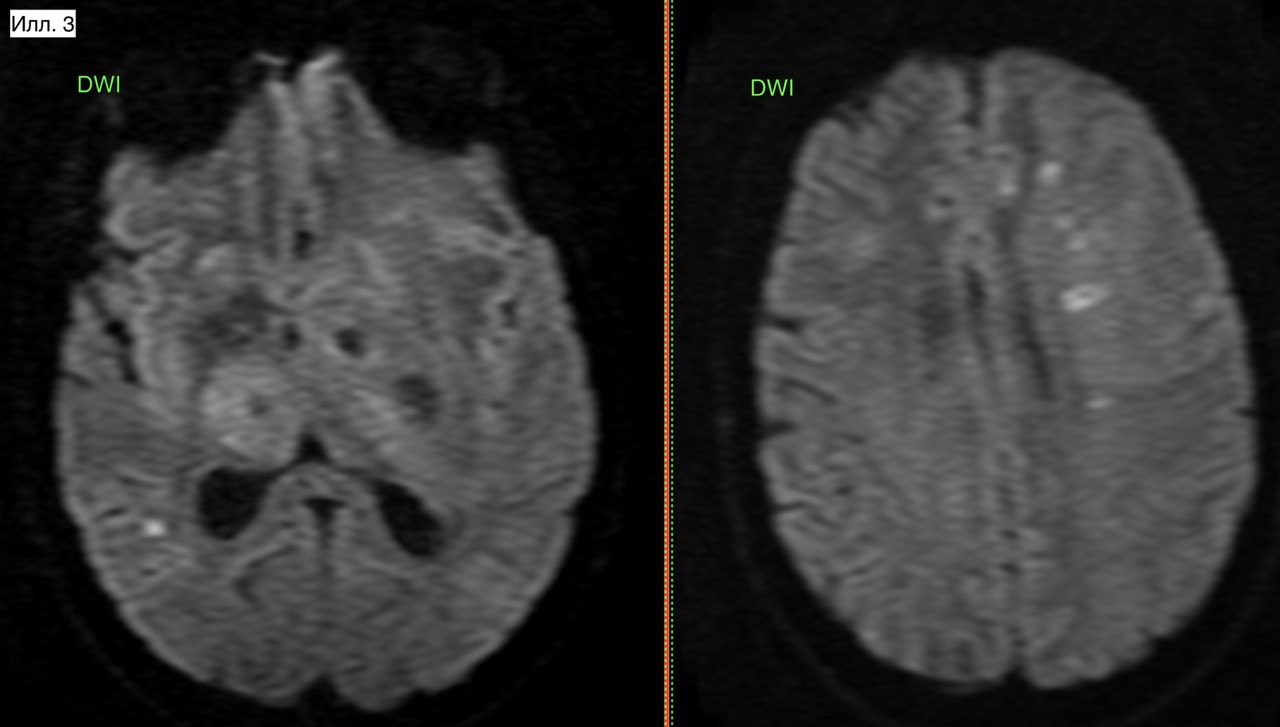

Пациент Ф., 18 лет. Пациент проходил обследование по направлению медкомиссии военкомата. Находка случайная, в анамнезе есть (вроде бы) ЧМТ. На илл. 1-2 хорошо определяется зона измененной структуры вещества мозга с увеличением объема пораженного участка. С учетом клинической картины (т.е. отсутствие каких-либо симптомов) заключение без дифференциального диагноза - опухолевое поражение. По картине это может походить на энцефалит, но напомню об отсутствии клинических знаков. Последствием ЧМТ это не может быть никак. В этой связи скиалогическая запись в заключении (илл. 3) не корректна, как вариант - использовать дифференциальный ряд и рекомендовать в/в контраст.

Илл. 1. Измененный участок на FLAIR (красные стрелки) имеет лишь очень небольшие изменения на DWI (круг). Для сравнения, случай 114 с токсоплазменным энцефалитом